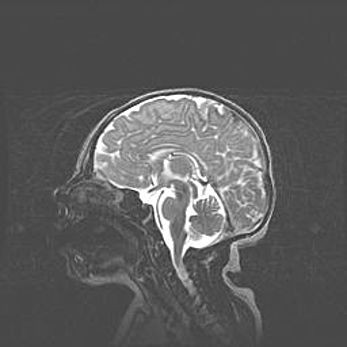

Церебральная ишемия II.

Возраст: 5 дней

Вес: 3400 г

Пол: женский

Окружность головы: 35 см

Срок гестации: 39 недель

Церебральная ишемия – это заболевание, характеризующееся недостаточностью (гипоксией) либо полным прекращением (аноксией) снабжения мозга кислородом по причине закупорки одного или нескольких сосудов. Это приводит к  что метаболическим расстройствам различной степени тяжести в тканях головного мозга, развитию коагуляционных некрозов и гибели нейронов.